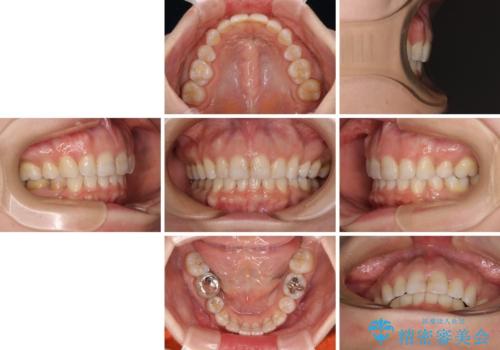

- 口元の閉じにくさと、奥歯の咬み合わせを気にして来院された患者様です。

左下の大臼歯2本が顕著に舌側に傾斜しているため、まずは奥歯の咬み合わせを改善をし、その後上下左右の第1小臼歯4本を抜歯することで口元を引っ込めながら整えることとしました。

奥歯の咬み合わせ改善には1年ほどの期間と処置中の噛みにくさを強いることとなりましたが、抜歯後はスムーズに治療を完了させることができました。

歯ぎしりの際に奥歯が干渉していた咬み合わせも理想的な状態に改善できました。